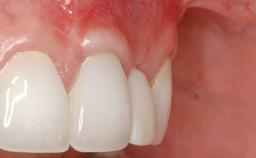

A 30-year-old woman was referred by her general dentist for evaluation of an esthetic complication related to previous implant treatment for congenitally missing maxillary lateral incisors. The patient’s chief complaint was the inadequate esthetic appearance of her smile. The case demonstrates the use of a combined approach to achieve optimal results. Two different flap designs - a tunnel technique and a coronally advanced flap - are employed based on the surgical objectives for the affected site.

Soft Tissue Grafting Yes

Soft Tissue Contour and Volume Slightly compromised